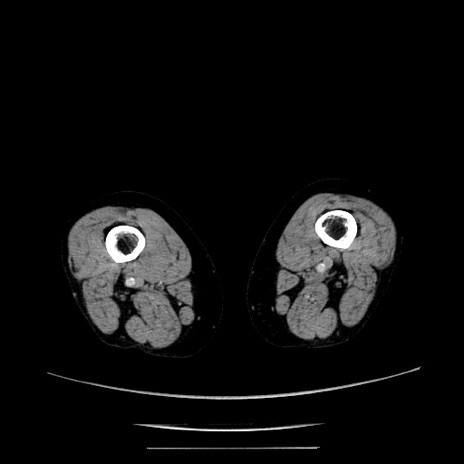

冠状断像

【症例】70歳代女性

【主訴】お腹が張る

【現病歴】1週間くらい前から腹部膨満の自覚あり。昨日夜から増悪したため、本日救急外来受診。

【身体所見】意識清明、BT 36.5℃、BP 165/106mmHg、HR 80bpm、SpO2 98%、腹部:膨満、軟、自発痛・圧痛なし、触診にて不快感あり、腸蠕動音:減弱

【データ】WBC 12600、CRP 1.04